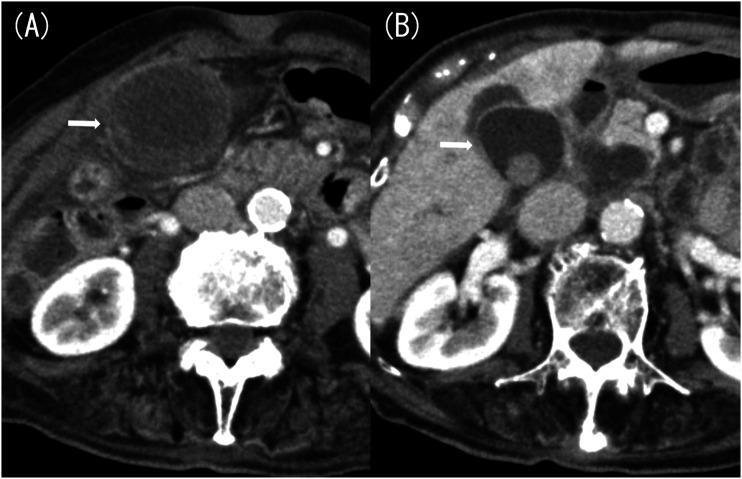

Cholecystitis is a common disease, but the occurrence of gallbladder strangulation is extremely rare. Here, we report a case of an 88-year-old woman with strangulated cholecystitis caused by an intraperitoneal band. Computed tomography (CT) scan revealed a constriction of the gallbladder body and marked wall thickening at the fundus. Additionally, the finding suggested torsion at the constricted area, which we diagnosed as gallbladder torsion. Cholecystectomy was performed immediately, and the diagnosis was strangulated cholecystitis caused by a band. The imaging findings of strangulated cholecystitis are similar to gallbladder torsion, making it difficult to diagnose preoperatively. We will discuss the imaging findings of strangulated cholecystitis and gallbladder torsion.